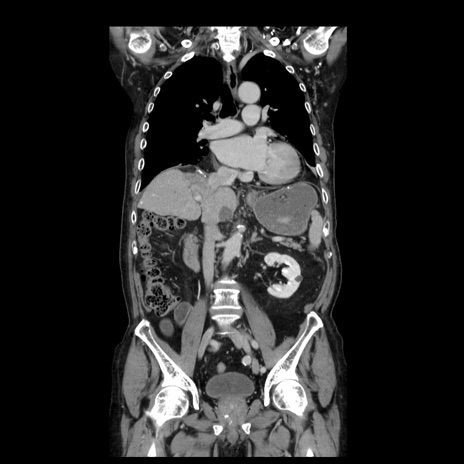

症例21(冠状断像)

【症例】70歳代男性

【主訴】腹痛

【現病歴】肝硬変・肝細胞癌にてかかりつけの方。約9時間前に食後より腹痛出現。症状が徐々に増悪し、嘔吐出現したため来院。

【既往歴】肝硬変、肝細胞癌(RFA、TACE後)

【身体所見】意識清明、表情苦悶様、BT 36℃、BP 129/78mmHg、P 88bpm、SpO2 97%(RA)、右上腹部から心窩部にかけて圧痛あり、反跳痛なし、筋性防御あり。

【データ】WBC 5800、CRP 0.16